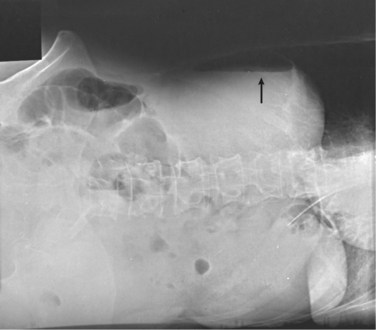

Structures shown: This projection shows the anatomy of the thorax, including the entire lung fields and any air or fluid levels that may be present (Fig. 28-13).

Fig. 28-13 Mobile AP chest radiographs performed in lateral decubitus positions in critically ill patients. A, Left lateral decubitus position. The patient has a large right pleural effusion (arrow) and no left effusion. Complete left side of thorax is visualized because of elevation on a block. B, Right lateral decubitus position. The patient has right pleural effusion (arrows), cardiomegaly, and mild pulmonary vascular congestion. Complete right side of thorax is visualized because of elevation on a block.